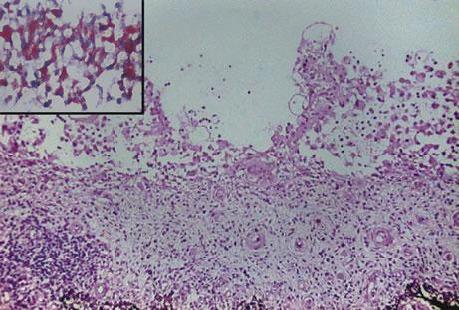

Juvenile xanthogranuloma (JXG) is a benign histiocytic skin disorder mainly encountered during infancy and childhood. Although with multiple potential localizations, less than 1% of the cases exhibit ocular manifestations. Some of these might lead to serious complications, specifically, secondary glaucoma that can result in severe and blinding eye disease. The aim of the present case report was to demonstrate typical clinical features, emphasize the difficulties attributed when managing these patients and literature review. We present the case of 4 months old female baby with spontaneous hyphema and secondary unilateral glaucoma due to ocular JXG. The natural history and treatment of the condition were extremely difficult to handle due to multiple opinions in histopathology related to other severe conditions that resembled with the lesions detected in this case: myelomonocytic leukemia and Langerhans cell histiocytosis. Although a minority of patients with JXG have ocular involvement, recognition of this condition is important because a treatment delay can lead to serious complications, such as glaucoma and spontaneous hyphema, as in our case. A thorough differential diagnosis represents the key to a proper management plan in these patients, both on short and long term. "Triple disease" defined as JXG plus neurofibromatosis type 1 (NF-1) and juvenile chronic myelogenous leukemia (JCML) has been reported, but it was not confirmed in our patient.

幼年性黄色肉芽肿(JXG)是一种主要在婴儿期和儿童期出现的良性组织细胞性皮肤疾病。尽管其可能有多个潜在发病部位,但不到1%的病例会出现眼部表现。其中一些可能会导致严重并发症,特别是继发性青光眼,可导致严重的致盲性眼病。本病例报告的目的是展示典型的临床特征,强调在管理这些患者时遇到的困难并进行文献综述。我们报告一例4个月大的女婴,因眼部JXG出现自发性前房积血和继发性单侧青光眼。由于组织病理学方面存在多种与该病例中检测到的病变相似的严重疾病(骨髓单核细胞白血病和朗格汉斯细胞组织细胞增多症)的观点,该疾病的自然病史和治疗极其难以处理。尽管少数JXG患者有眼部受累,但认识到这种情况很重要,因为治疗延迟可能导致严重并发症,如青光眼和自发性前房积血,就像我们的病例一样。全面的鉴别诊断是这些患者短期和长期合理管理计划的关键。已报道有“三联病”,定义为JXG加1型神经纤维瘤病(NF-1)和幼年慢性粒细胞白血病(JCML),但在我们的患者中未得到证实。